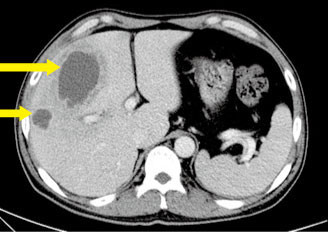

간농양(liver abscess): 간에 생기는 고름집, 증상, 원인, 치료 및 예방

간농양은 간에 생기는 고름집입니다. 세균, 기생충, 곰팡이 등의 감염으로 인해 발생하며, 급성 또는 만성으로 진행될 수 있습니다. 급성 간농양은 진행되어 심각한 증상을 유발할 수 있고, 만성 간농양은 장기간 지속되며 간 손상을 유발할 수 있습니다.